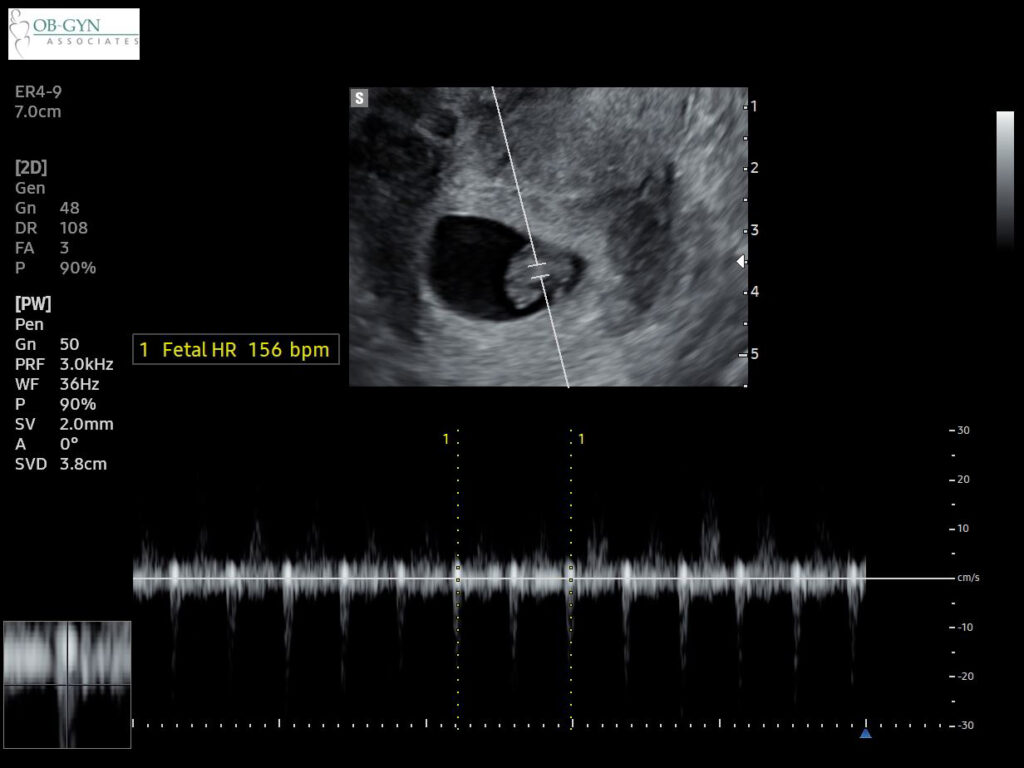

We found out we were pregnant just before Thanksgiving and heard the heartbeat at our first ultrasound when I was 7W3D. I cried the moment I heard it – happy tears, of course. I stared at the ceiling during that appointment instead of the screen ahead until I heard the good news from the ultrasound tech. It felt incredible to finally have a beautiful ultrasound appointment (I switched doctors since our last experience and am so grateful for the compassionate people at this new practice).

Update: We heard the heartbeat at our 10 week checkup!